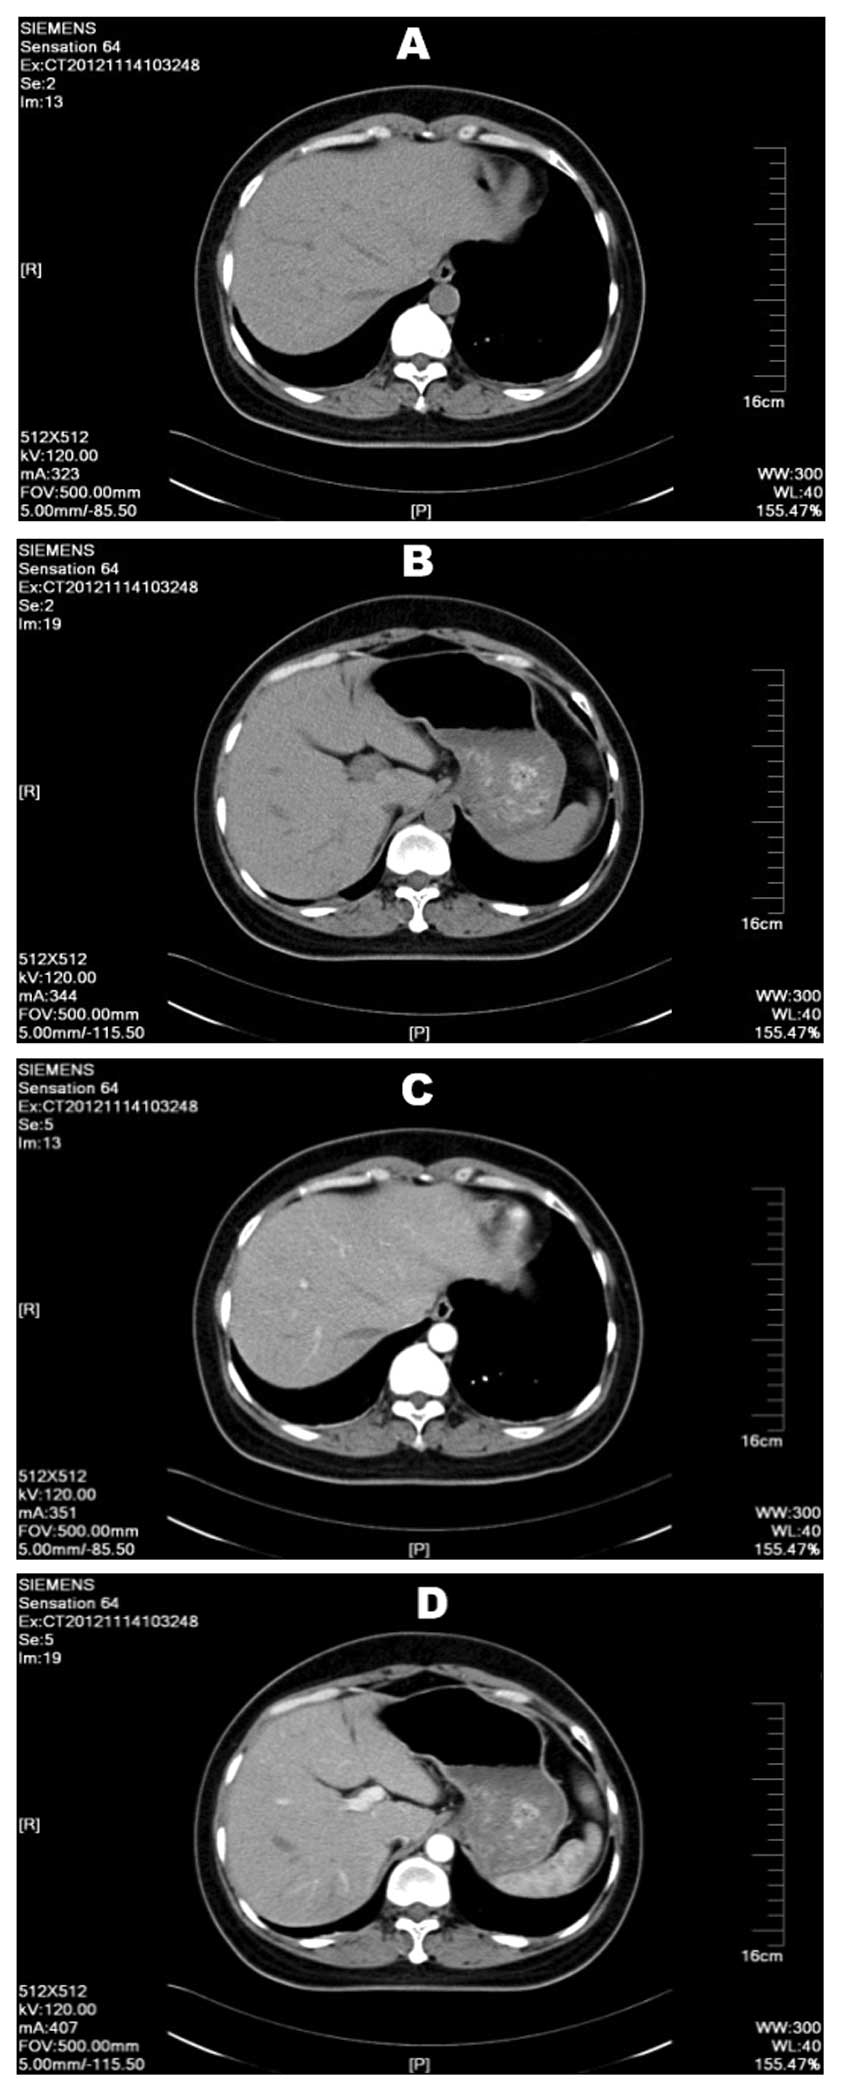

Subsequent examinations were performed to yield further information to base the developing diagnosis on. Several tumor markers were negative, including α-fetoprotein (AFP), carcinoembryonic antigen, cancer antigen (CA)19-9, CA12-5 and CA15–3. These tumor markers were measured again 1 month later and were again found to be negative. Tests for the antigens and antibodies of hepatitis B and C were all negative. Abdominal B-mode ultrasound indicated that the liver was normal and no abnormal signals were observed. Examinations after 3 months and again after 12 months by abdominal B-mode ultrasound showed no subsequent anomalies. Upper abdominal plain and enhanced CT scans revealed a slightly lower density mass in the right hepatic lobe that was not well defined. The mass was ~9×7 mm, and as the only anomaly within the liver, this site was suspected as the primary liver hemangioma (Fig. 3), however, no positive diagnosis could be made. The patient had no history of chronic liver disease in the past.

Figure 3.

Upper abdominal plain and enhanced CT scans revealing a slightly lower density mass in the right hepatic lobe that was not well defined, with a size of ~9×7 mm. Plain CT at (A) 13 mm and (B) 19 mm levels; enhanced CT at (C) 13 mm and (D) 19 mm levels. CT, computed tomography.

Given the clinical presentation and imaging results of the patient in the present study, lipomyoma was the most likely diagnosis. During surgery, a yellowish soft mass was found and removed from the spinal canal. This was believed to be the mass indicated by the MRI in Fig. 1, unfortunately no sample was preserved after removal. Unexpectedly, the immediate histopathological examination revealed a moderately-differentiated HCC. Pathological diagnosis is considered as the gold standard diagnostic technique, however, the results were not in accordance with the previous imaging diagnosis and intraoperative exploration findings. The pathology results were rechecked three times, yet each time the results pointed to an HCC. The immunohistochemical markers indicated that it was moderately-differentiated, yet subsequent laboratory examinations indicated almost nothing abnormal in the patient's liver. CT was the only modality that indicated a small area of slightly lower density in the right hepatic lobe, measuring ~9×7 mm. This region was highly suspicious, however, tumor markers were negative and abdominal ultrasound suggested normal tissue. The patient continued to undergo abdominal ultrasound scans every 6 months without any indication of anomalies. Given that ultrasound is an extremely sensitive indicator for liver carcinoma, this led us to conclude that no primary site within the liver could be located that agreed with the pathology results. According to the CT results and the pathological examination, we have several hypotheses about the primary site. Firstly, in the embryonic period of the patient, the gene-mutated liver cancer cells may have metastasized or been implanted in the spinal canal, and over time the tumor mass would have compressed the spinal canal and the patient would begin to express symptoms. Secondly, the low-density mass in the liver found by CT could have been the primary foci, but due to the small size, examinations may have failed to recognize that it was a tumor mass. It is also possible that the size of the primary tumor affected the tumor marker test, as the AFP sensitivity decreases from 52 to 25% as the tumor diameter decreases below 3 cm (9).